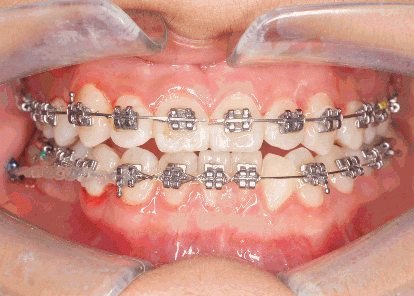

牙齒矯正流程

第二步:復診

一般而言患者需要一個月進行一次復診,由正畸醫(yī)生檢查治療情況及口腔衛(wèi)生狀況,進行相應的調(diào)整及口腔衛(wèi)生宣教,選擇隱形矯治的患者可適當延長復診周期,但一般不得超過三個月。

第三步:摘牙套,戴保持器

當正畸目標得到實現(xiàn),患者對正畸治療效果表示滿意時,就可以拆除正畸治療裝置(托槽,附件等),但這并不意味著正畸流程的結(jié)束,在拆除托槽之后,要求患者仍持續(xù)佩戴保持器兩年左右,若原先情況較復雜可延長佩戴保持器的周期。